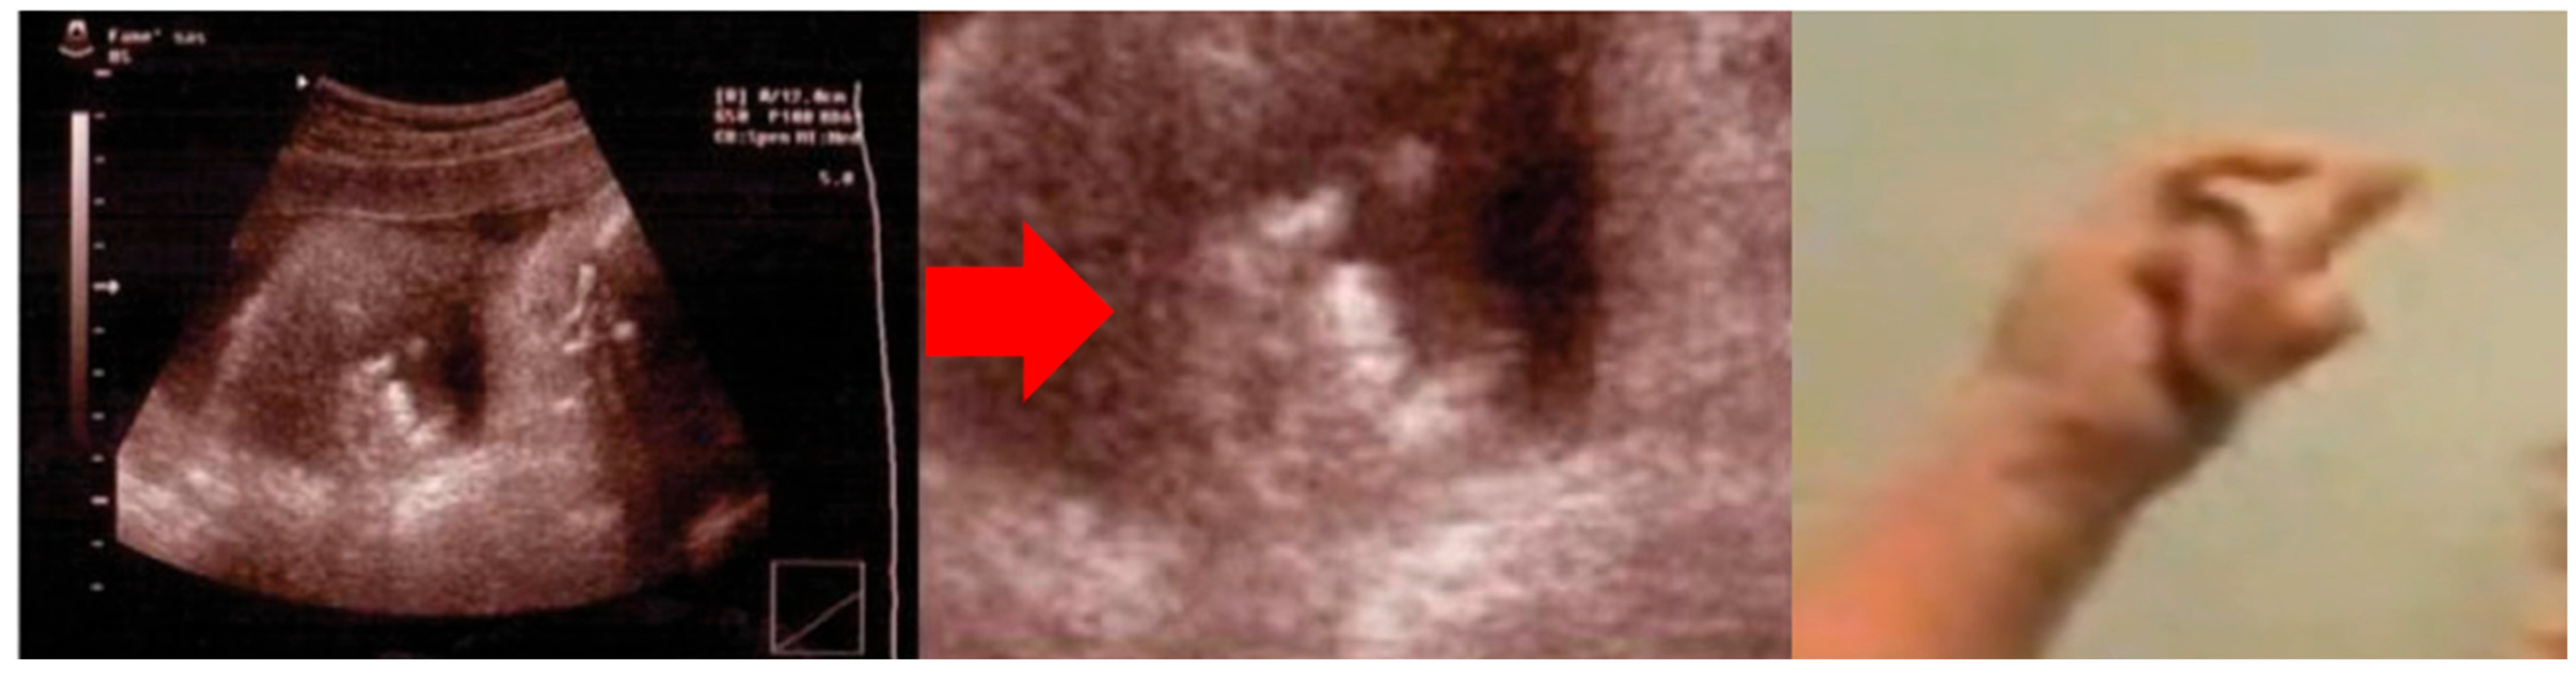

3.1. Patient #1

| Evidence prompting suspicion of cs/ciss | Orofacial muscle contractions, generalized paroxysmal events, camptodactyly | Prenatal bilateral camptodactyly |